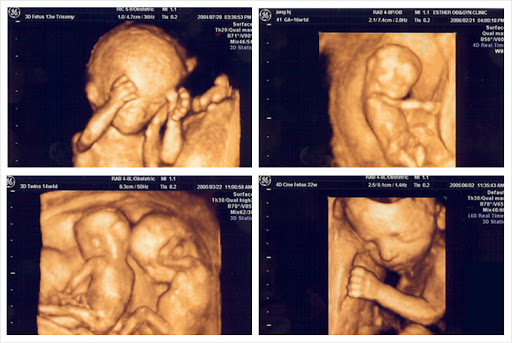

위의 사진은 아기의 초음파 사진이다.

엥 초음파 사진의 경우 항상 흑배사진이라며?

맞다 모두 흑백사진이다. 위의 사진에 color가 보이는

이유는 병원에서 인위적으로 색을 입힌것이다.